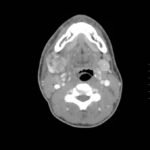

The computed tomography (CT) scan demonstrates prominent enlargement and heterogeneous enhancement of the right submandibular gland (single large arrow) compatible with sialadenitis. There is no evidence of a sialolith or obstruction on the CT. There is associated edema (two small arrows) of the right submandibular space, parapharyngeal space and anterior right neck with partial effacement of the right vallecula and right pyriform sinus.